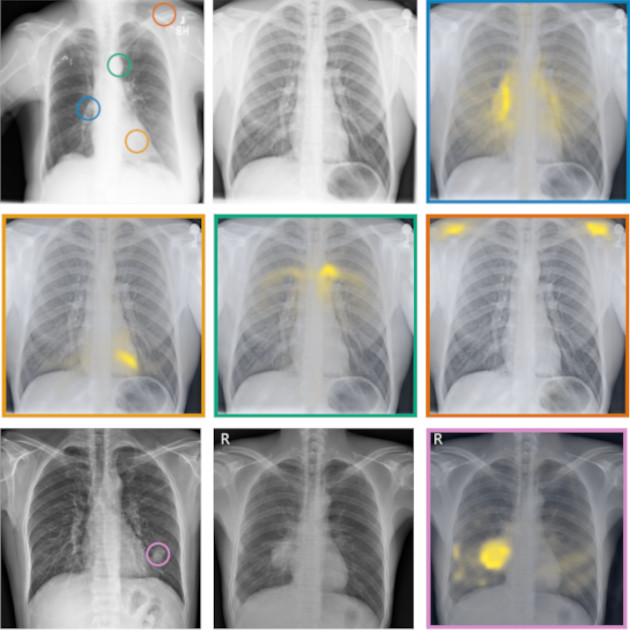

RadEdit: stress-testing biomedical vision models via diffusion image editing

F. Pérez-García, S. Bond-Taylor, P.P Sanchez, B. van Breugel, D.C. Castro, H. Sharma, V. Salvatelli, M.T. Wetscherek, H. Richardson, M.P. Lungren, A. Nori, J. Alvarez-Valle, O. Oktay, M. Ilse